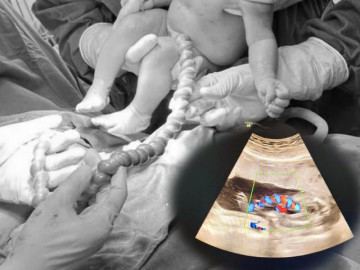

Thấy hình ảnh siêu âm bất thường của thai phụ 20 tuổi, bác sĩ chỉ định mổ lấy thai khẩn cấp

Xoắn dây rốn (hay cả thắt nút dây rốn) là một trong những biến chứng thai kỳ hiếm gặp nhưng khá nguy hiểm, nếu không phát hiện và xử trí kịp thời, tình trạng này thậm chí có thể đe dọa tính...